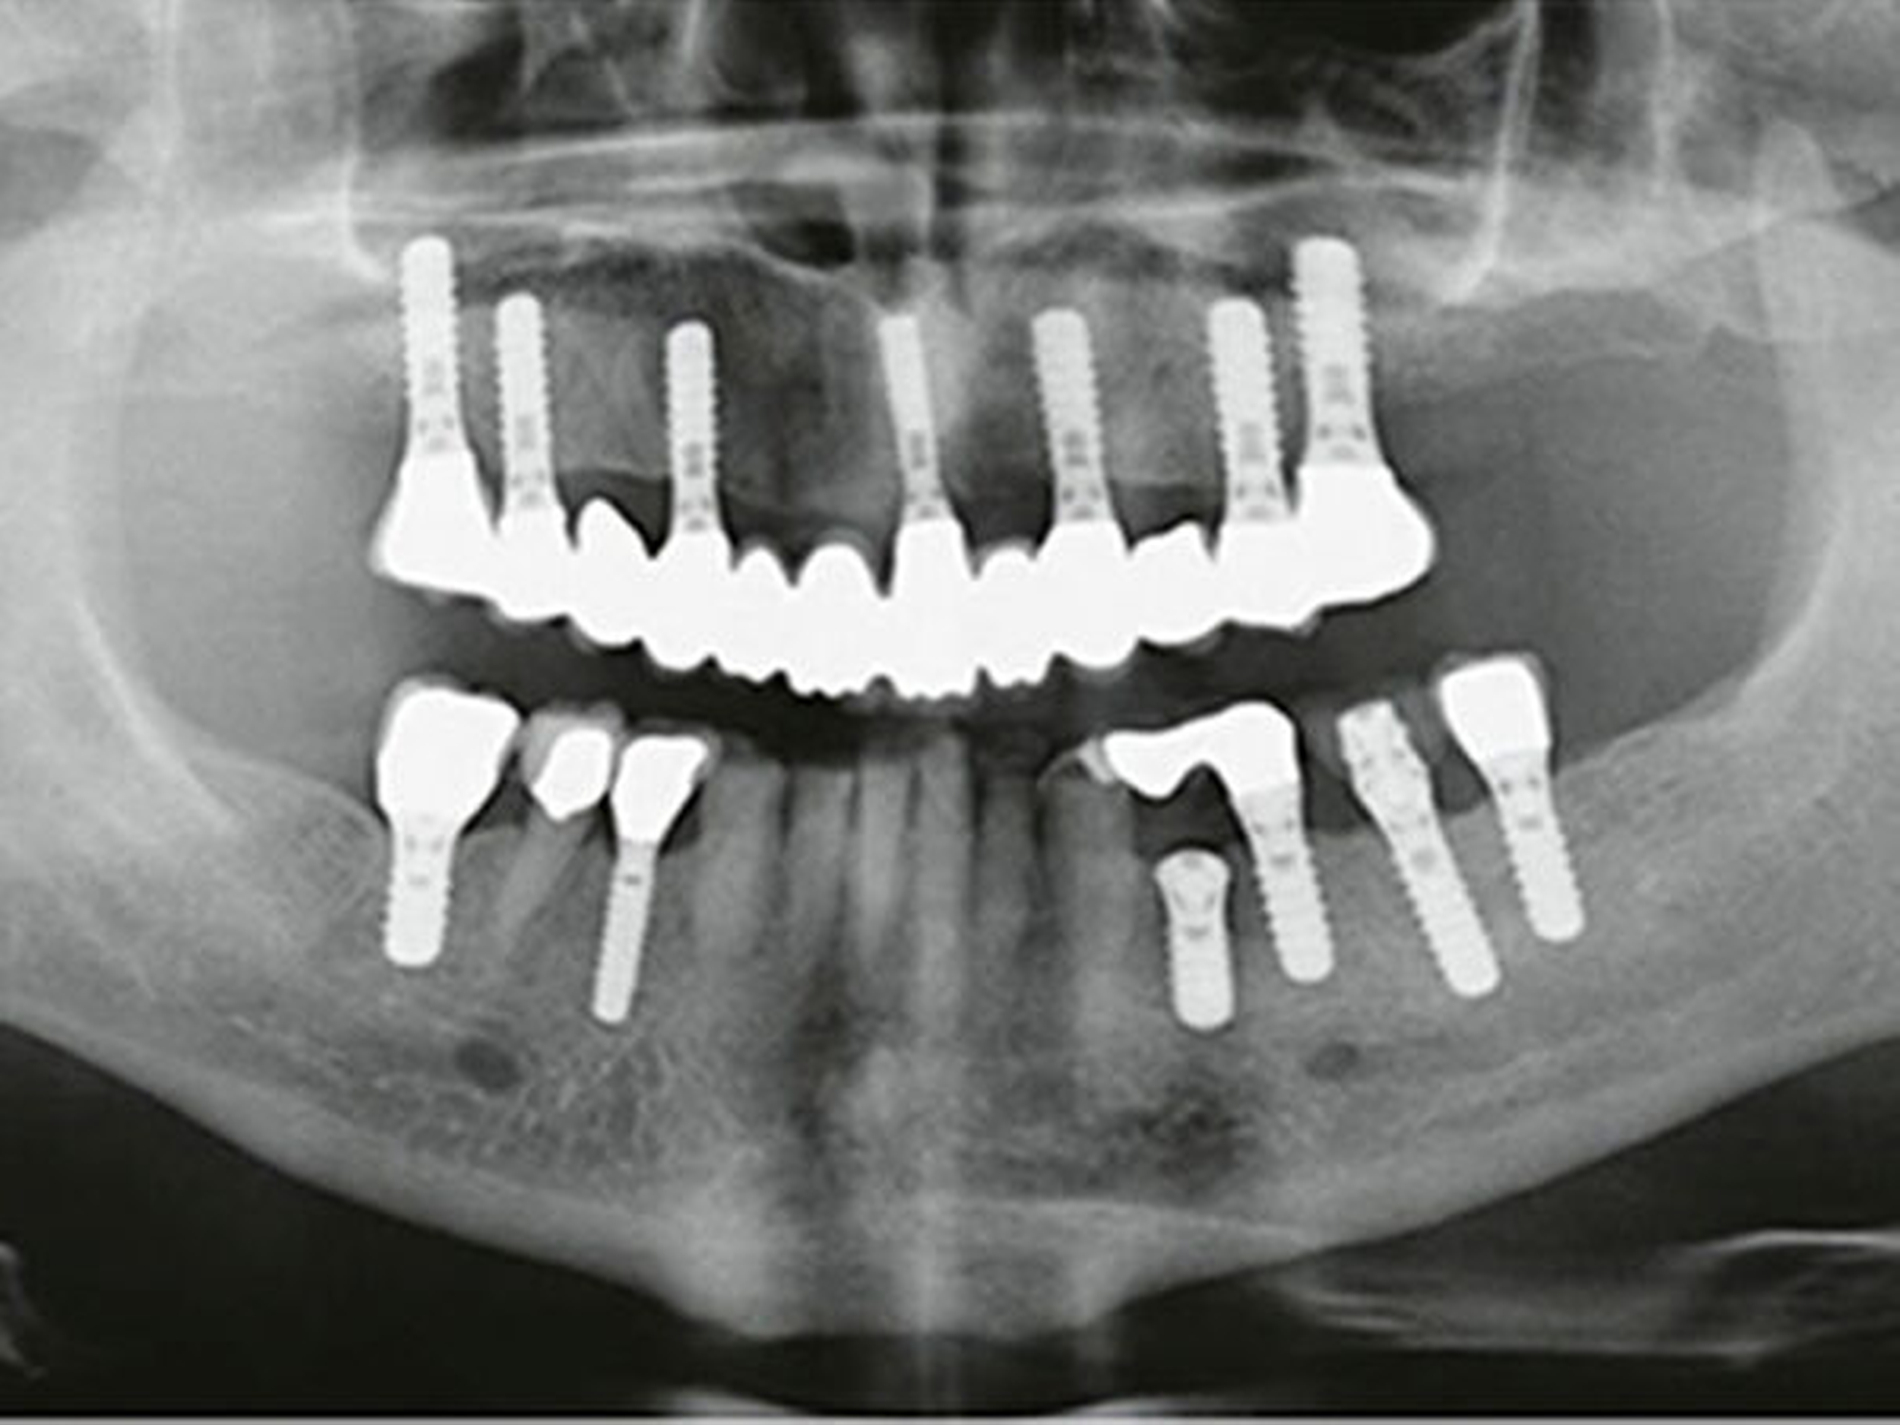

Eine 68-jährige Patientin erschien in unserer Sprechstunde zur Erstuntersuchung mit dem Wunsch nach einer ästhetischen Versorgung ihrer Unterkieferfrontzähne mit Veneers. Die Patientin war in der Vergangenheit alio loco im Oberkiefer mit einer verschraubten Brückenkonstruktion auf sieben Implantaten und im Unterkieferseitenzahnbereich im Bereich der Zähne 34–37, 44 und 46 ebenfalls mit implantatgetragenen Restaurationen versorgt worden. Natürliche Zähne existierten nur noch im Frontzahnbereich (33–43) und im Bereich des zweiten Prämolaren auf der rechten Unterkieferseite (Abb.1).